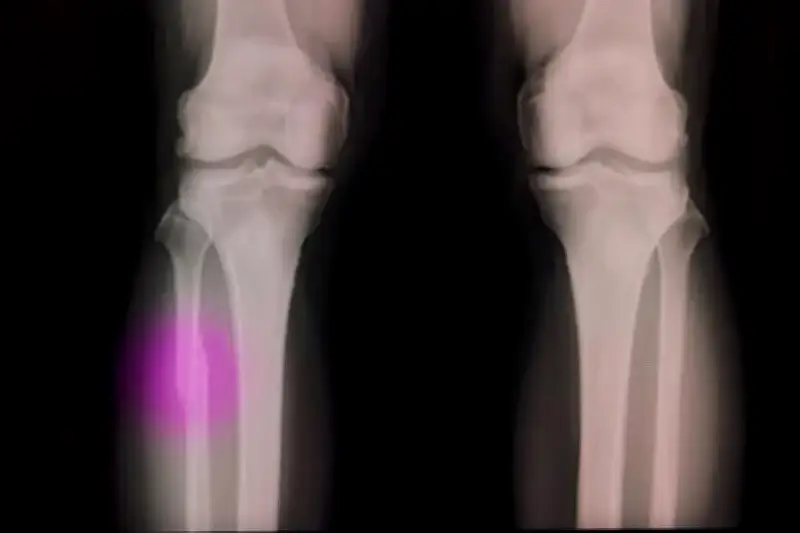

খেলাধুলা বা দুর্ঘটনায় হাত-পা ভাঙা একটি সাধারণ ঘটনা, বিশেষ করে কিশোর-কিশোরীদের মধ্যে। এতে প্লাস্টার, অস্ত্রোপচার এবং দীর্ঘদিনের বিশ্রামের প্রয়োজন হয়, যা রোগীর জন্য কষ্টদায়ক। কিন্তু বিজ্ঞানীরা এবার একটি অভিনব সমাধান নিয়ে এসেছেন যা এই সমস্যা মোকাবিলায় বিপ্লব আনতে পারে।

অস্ট্রেলিয়ার একদল গবেষক একটি বিশেষ ধরনের জৈব আঠা এবং থ্রি-ডি প্রিন্টিং কলম বা গ্লু গান তৈরি করেছেন, যার নাম দেওয়া হয়েছে বায়োপেন। এই গ্লু গান ব্যবহার করে চিকিৎসকেরা ভাঙা হাড়ের জায়গায় বিশেষ জেল বা আঠা লাগাতে পারেন। এরপর অতিবেগুনি রশ্মি বা বিশেষ আলো ফেললে সেই আঠা দ্রুত শক্ত হয়ে হাড়ের মতো মজবুত কাঠামো গঠন করে।

এই প্রক্রিয়াটি ঐতিহ্যবাহী পদ্ধতির চেয়ে অনেক বেশি কার্যকর এবং কম সময়সাপেক্ষ। রোগীদের আর মাসের পর মাস প্লাস্টার বা মেটাল স্ক্রু-পাতের যন্ত্রণা সহ্য করতে হবে না। বায়োপেনের মাধ্যমে হাড় জোড়া লাগানো হয় নিখুঁতভাবে, যা দ্রুত সুস্থতা এবং কম জটিলতা নিশ্চিত করে।